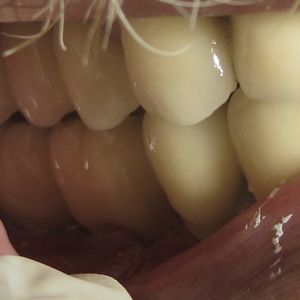

Prosthetic rehabilitation: once osseointegration is complete, an abutment and permanent crown, bridge, or denture is placed on the implant. Prosthetic rehabilitation on implants is our core specialty and is key to the long-term success of the treatment.